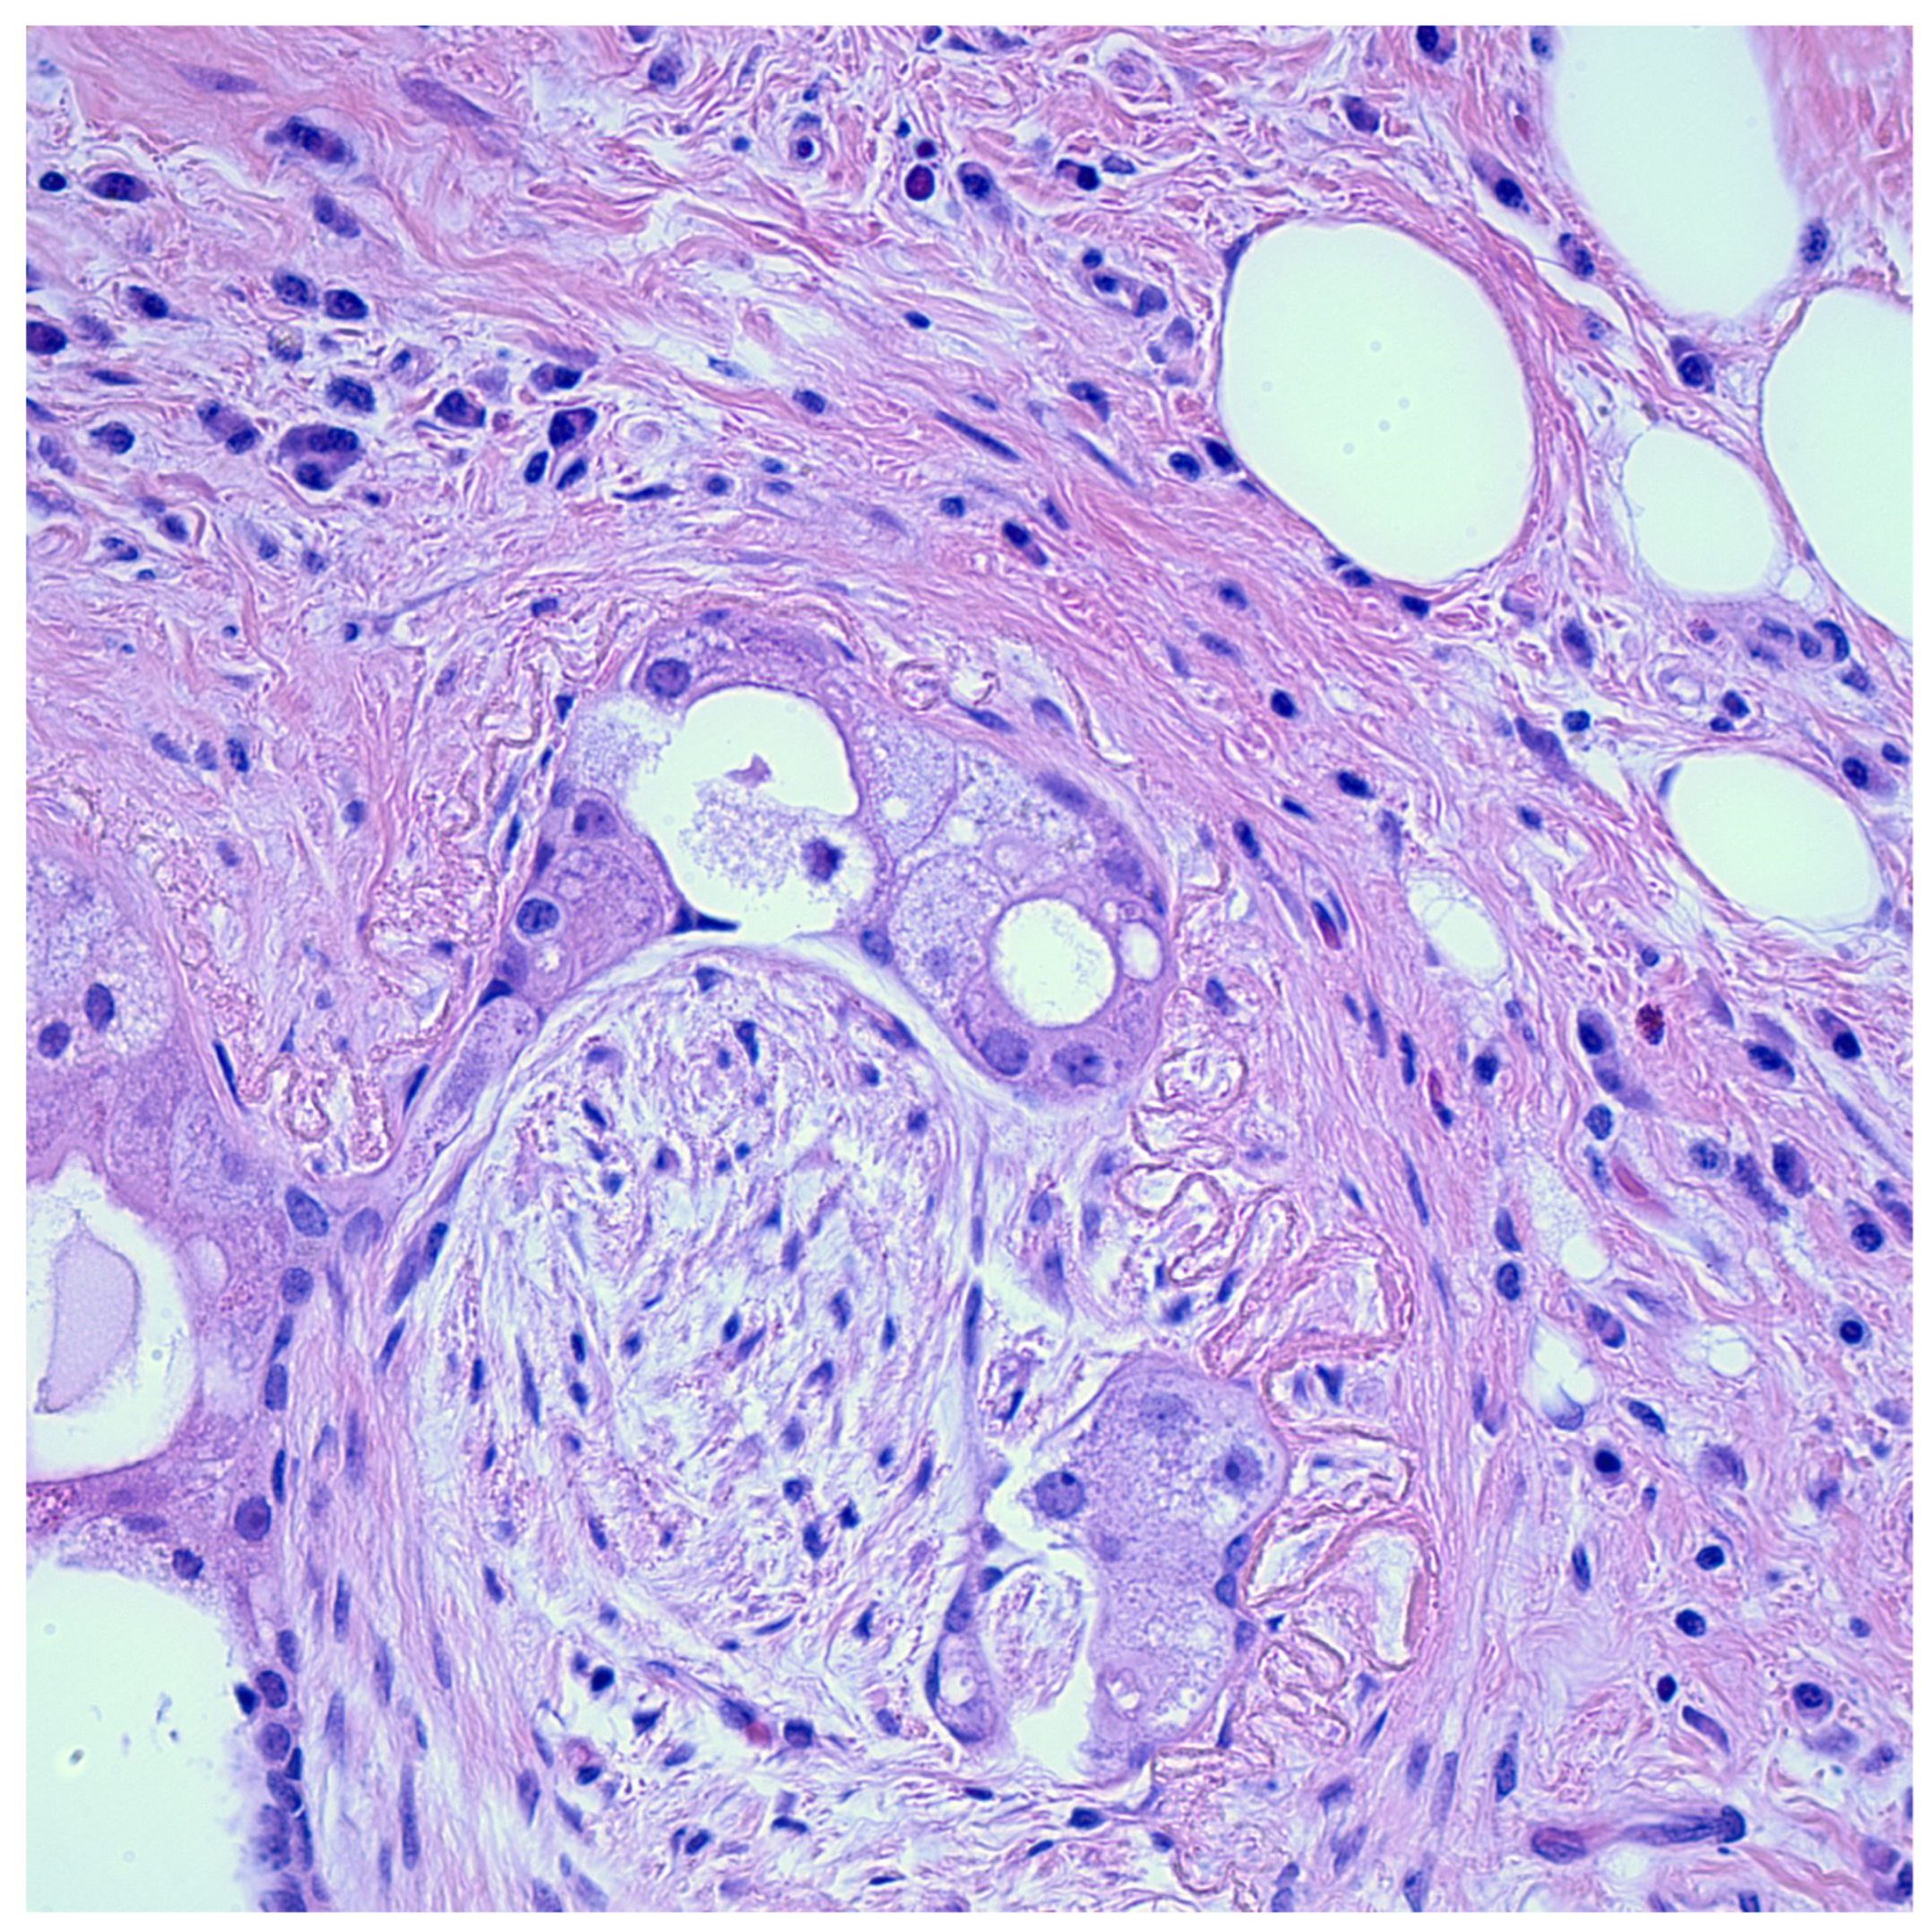

Perineural invasion (PNI) is defined as the dissemination of neoplastic cells within the perineural or intraneural space [1] (Figure 1). This allows the associated nerves to act as a pathway for metastasis, even in cases where blood or lymph metastasis is absent [2]. Tumor cells may be found in any layer of the nerve sheath; however, perineural involvement should also be suspected in tumors in close proximity to a nerve that is at least one-third the size of the nerve’s circumference [3]. Thus, this phenomenon can be classified into four subtypes based on the extent of involvement: tumor cells in proximity to nerves; tumor cells encircling nerves less than 33%; tumor cells encircling nerves greater than 33%; and tumor cells infiltrating the nerve sheath [4].

After a review of the literature, two reports were found of pleomorphic adenomas of the parotid gland containing PNI. Selesnik and Burt described five head and neck malignant neoplasms and one benign parotid gland adenoma demonstrating PNI [133]. Roncati and Maiorana described a case of a 30-year-old woman with a recurrent pleomorphic adenoma of the parotid gland with PNI [134]. A report by our group also described a case of a 73-year-old woman with a left parotid gland mass, which—upon examination—was diagnosed as a sclerosing polycystic adenoma with evidence of perineural entrapment [135] (Figure 4).